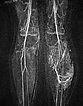

Contrast-enhanced MR angiography (MIP) shows complete enhancement of the venous malformation component in the left calf with contrast pooling.

The control MR angiography shows a clear improvement of the findings. Most of the dysplastic, dilated channels of the venous malformation are occluded.